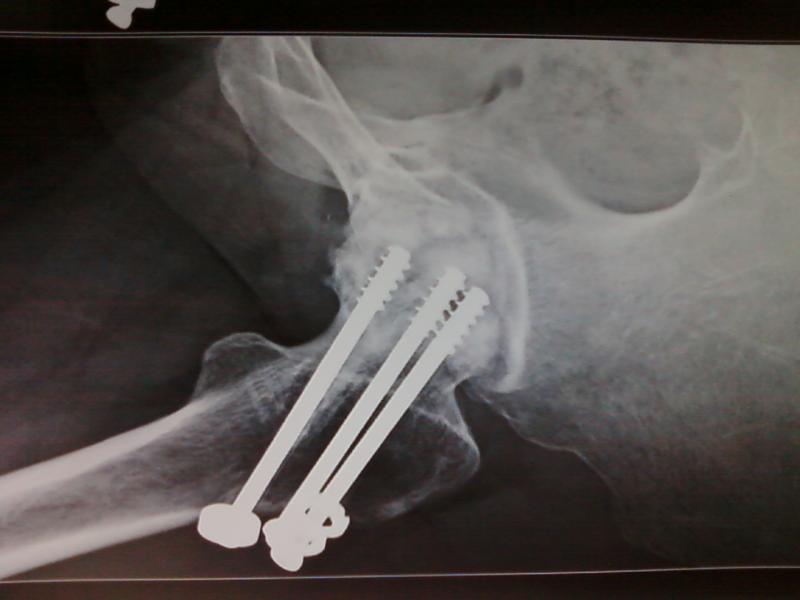

AVN Post Surgery.... Successfully Replaced